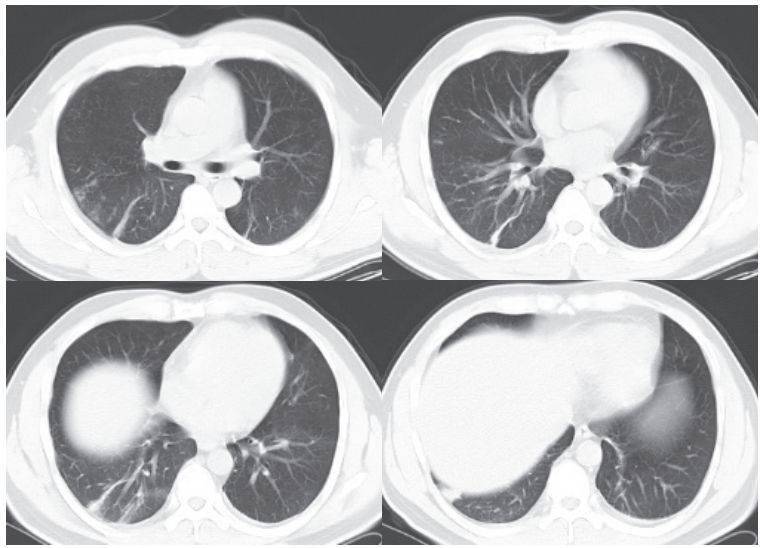

二、进展期征象

新冠肺炎大多数病例进展迅速,复查 CT 影像发生明显变化

表现为病灶数目明显增多,范围明显扩大,密度增高,病灶分布由外周向中央推进

根据既往 SARS 病理学机制,提示为肺泡腔内聚集大量细胞渗出液、间质内血管扩张渗出;肺泡连通起来形成融合态势(图 2-11)

图 2-11 病灶数目增多、范围扩大 (A-D)